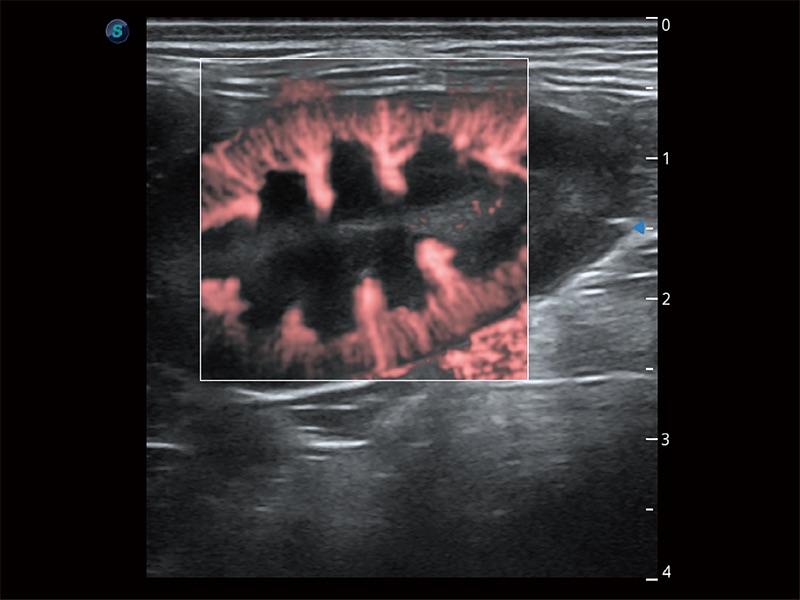

极大提升超低速微细血流的检出能力,同时更精准地滤除软组织和超声信号,为兽用医生提供以往无法通过常规血流获得的疾病诊断信息。

在传统二维血流成像的基础上,呈现血流的立体感,具有动感的生命力之美。即便是微小的血管也能轻松应对,提高了血流的视觉敏感性。

非线性融合造影成像充分利用谐波和基波信号,为难以观察的血流进行增强显像。可用于线阵、凸阵、微凸阵、相控阵探头。